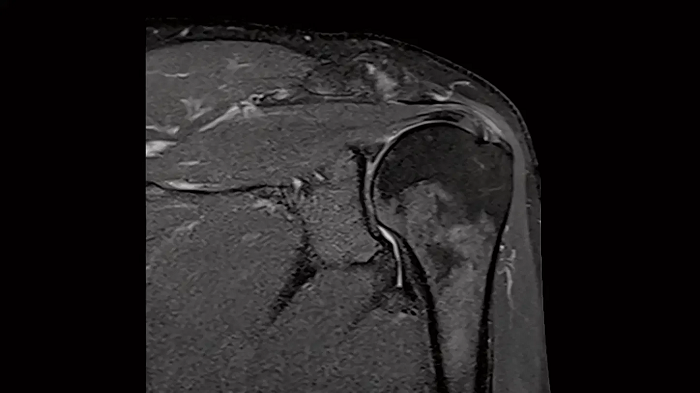

Shoulder

Shoulder - PD TSE FatSat

Exceptional fat suppression for the clear imaging of the shoulder.

• Contour S Coil

80 cm bore MAGNETOM Free.Max

Image Courtesy: University Hospital Erlangen, Germany | Image-ID: 4aaaa0384